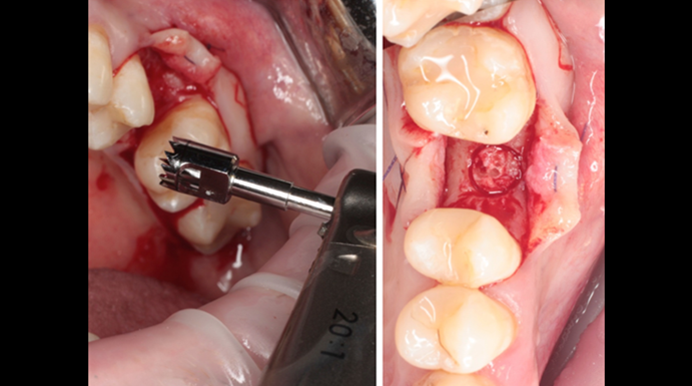

Clinical case: # 46 implant placement & GBR using i-Gen membrane for significant vertical resorption & mixed bone defect

- Courtesy of Dr. Iulian Filipov, Romania -

AnyRidge, mandibular posterior, i-Gen, resorption, bone defect, bone regeneration, space management, #46, GBR, Dr. Iulian Filipov

AnyRidge implant system, i-Gen